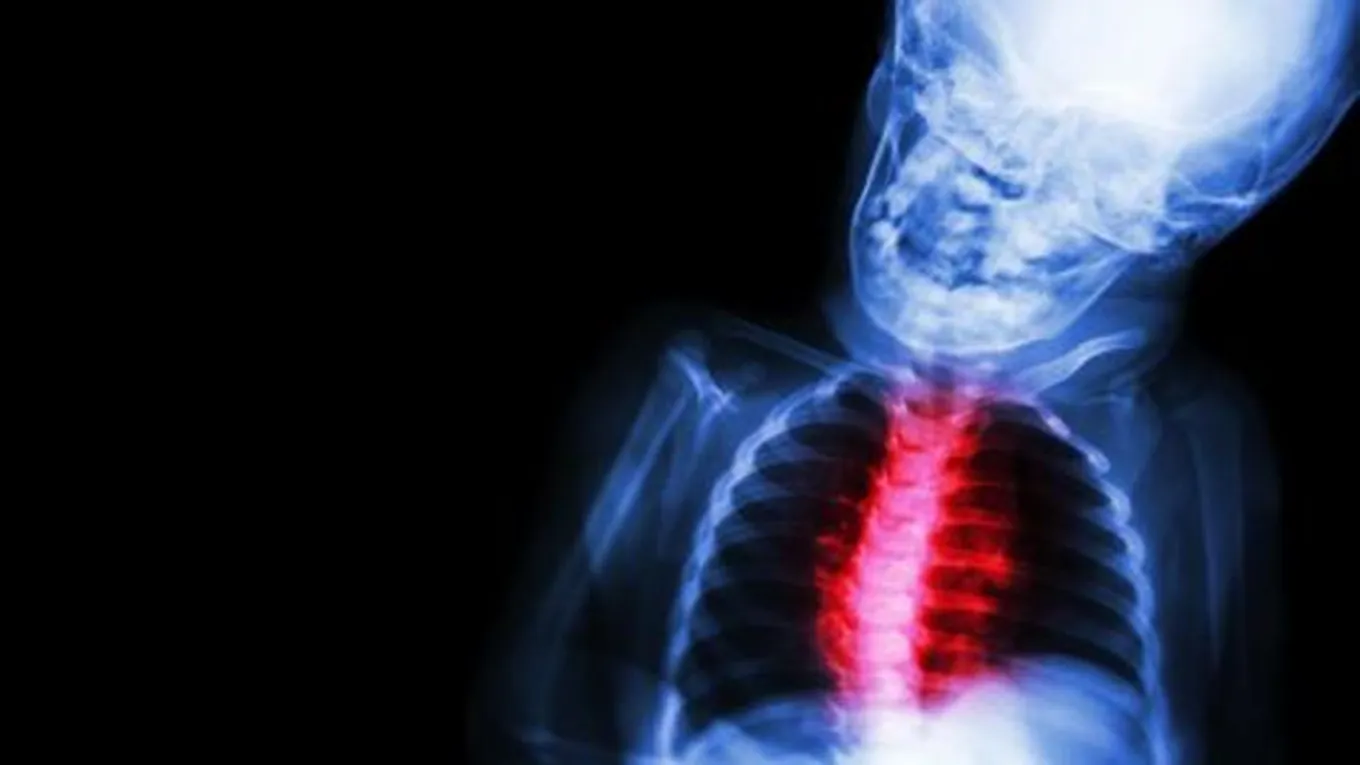

يعتبر روماتيزم القلب أحد الأمراض التي تصيب الأطفال بشكلٍ خاص، وهو ناتج عن التهابات شديدة وحادّة في الأنسجة المحيطة للقلب، ويكون سببه الرئيسيّ الإصابة ببكتيريا ستبتوكوكس والتي تبدأ بصامامات القلب، ثمّ تصيب باقي أنحاء الجسم بما فيها اللوزتين، وفي حال لم يتمّ علاجه بالشكل الصحيح يُمكن أن يؤدي إلى الإصابة ببعض الأمراض القلبية التي تؤدي إلى الوفاة، وفي هذا المقال سنتحدث عن أعراضه، وأسبابه، وطرق علاجه.

القلب هو عبارة عن مضخة تتكوّن من أربع غرف، ويوجد بداخل كلّ غرفة صمام معين، وتقوم هذه بالفتح والإغلاق بجهة واحدة، حتى لا يتدفّق الدم إلى وراء القلب، وفي حال الإصابة بروماتيزم القلب فإنّ صمام القلب يكون تالفاً، بالتالي فإنّه لا يؤدي إلى تدفّق الدم بشكلٍ صحيح، لذلك فإنّه يُسبب العديد من الأمراض مثل: التهاب شغف القلب، والسكتة الدماغية التي تنتج عن إغلاق الأوردة الدموية في الدماغ، والوفاة في الحالات المتقدمة.